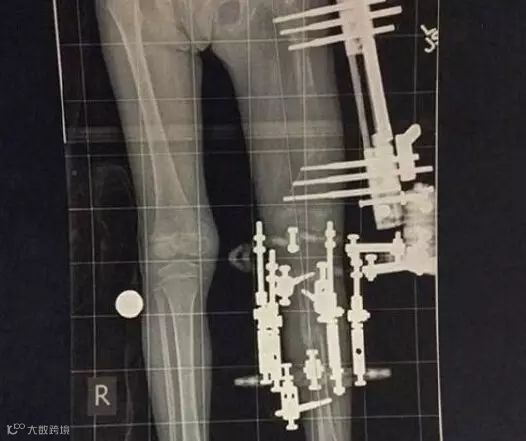

但是那只是一切折磨的开始。三岁的时候她得经历另一场手术,那是一场分开她大腿和小腿骨头的外科手术。手术之后,她的腿会通过皮肤、肌肉和骨头被安装上外固定器与十针穿刺装置。为了避免恢复过程中的碰撞,Jackie得手动旋转设备上的螺丝,每天将股骨和胫骨骨之间的距离调整0.039英寸。

只有这样做,Elsie才能在缝隙之间长出新的骨头、肌肉和皮肤,然后她的腿也会在四个多月的时间里慢慢变长4英寸。在这段时间里,这个小女孩必须不断通过止痛药来承受这个痛苦想要拥有傲人身姿吗?!